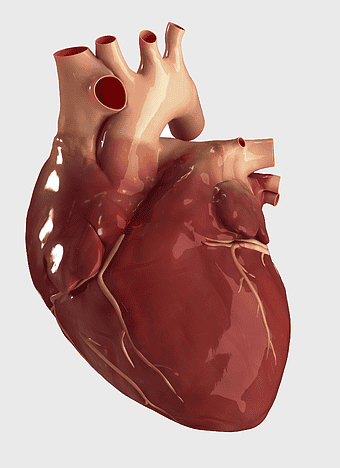

Heart Anatomy Diagram, human heart drawing, realistic heart illustration, cardiovascular system, medical illustration, organ structure, human anatomy study -

human heart anatomy, cardiovascular system illustration, medical heart diagram, heart organ structure, human body organ visuals, anatomical heart drawing, heart health -

human heart anatomy, cardiac muscle illustration, circulatory system model, heart health visual, cardiovascular organ diagram, medical heart image, visceral structure depiction -

Heart Anatomy Atrium, Aortic arch Human body, human circulatory system, ventricle and heart阀, cardiovascular health, thoracic cavity structures, heart valve functionality, atrium blood flow diagram -